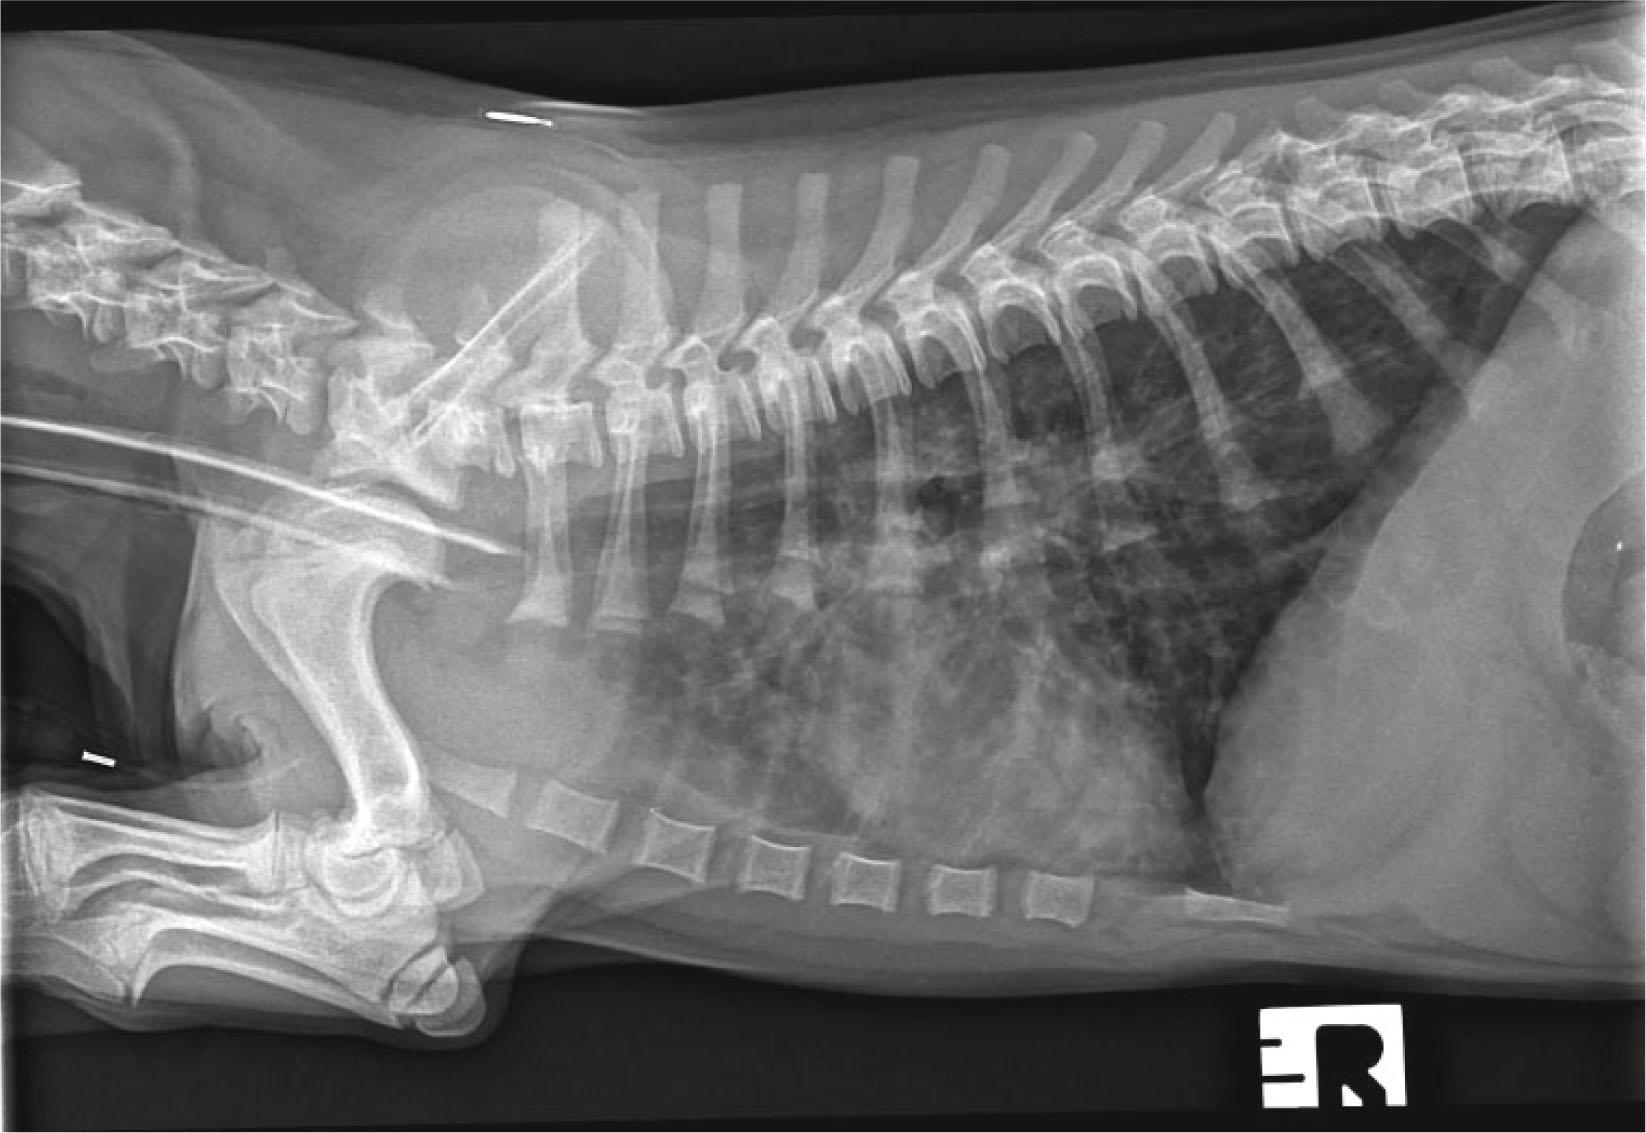

Lateral and dorso-ventral radiographic projections of the thorax were taken at full inspiration, revealing a normal cardiac silhouette, enhancement and thickening of the bronchial walls spreading into the periphery of the lung fields, and a diffuse increase in pulmonary opacity throughout the lungs (Fig. 1). Flexible bronchoscopy was performed and visualization of the trachea and bronchioles revealed a moderate quantity of mucous and absence of foreign bodies, nodules or masses. After inspection of all primary and secondary bronchioles, a bronchoalveolar lavage (BAL) was performed. During the instillation, a single motile white worm was observed on the mucus of the bronchial wall and cytological evaluation of the BAL showed the presence of a non-septic exudate with marked eosinophilic infiltration.

Fig. 1

Right lateral thoracic radiograph of the dog showing thickening of the bronchial walls into the periphery of the lung fields and a diffuse increase in pulmonary opacity throughout the lungs